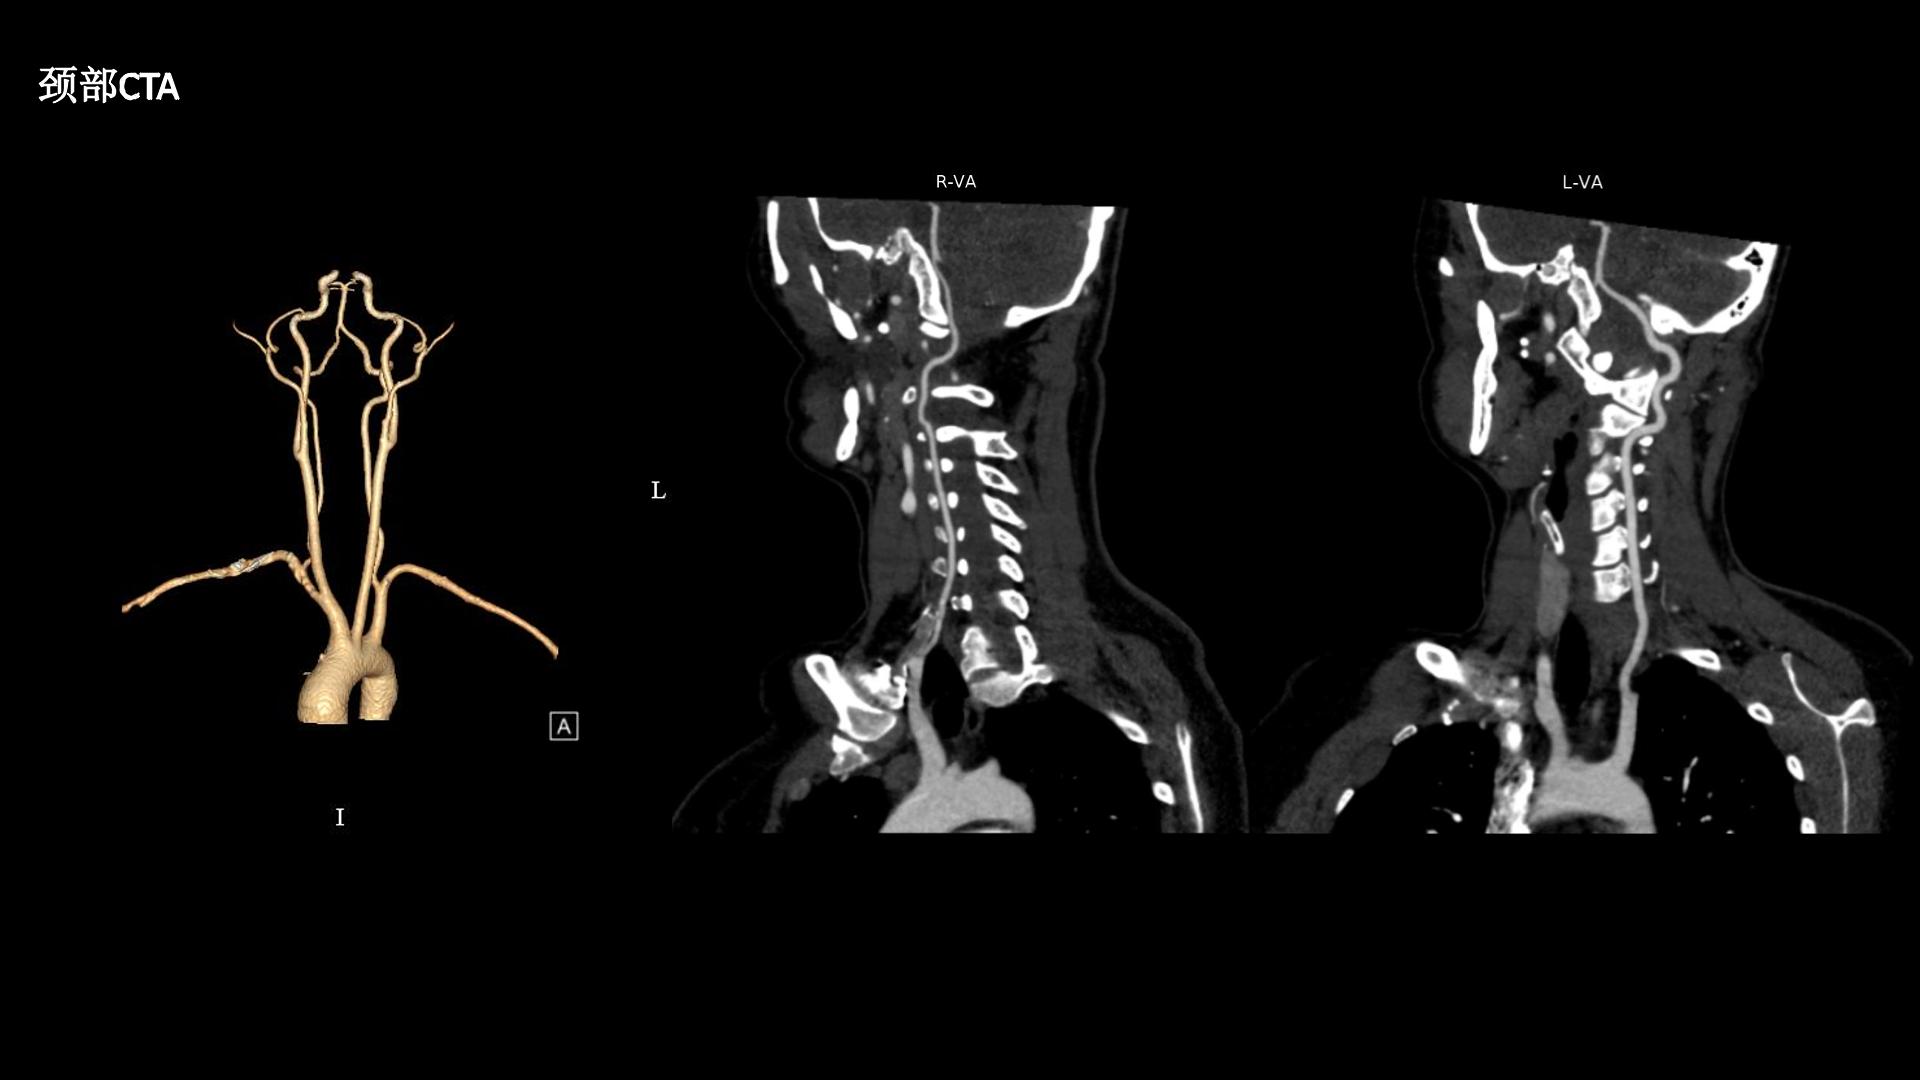

西安交通大学第二附属医院刘重霄教授团队:一例巨长型颈胸椎神经鞘瘤切除术+脊柱内固定术